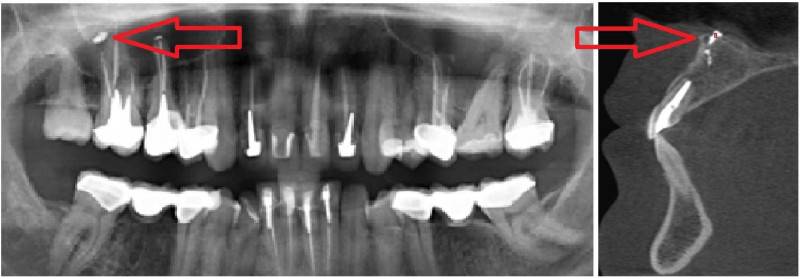

Стрелками показаны фрагменты пломбировочного материала (вид спереди и сбоку), который при пломбировании канала выпал за пределы зуба и «упёрся» в область залегания ветви тройничного нерва. У пациента долго болел зуб после лечения пульпита, затем онемела верхняя губа и часть щеки.

Стрелками показаны кисты корней зубов (вид спереди). Кисты в данном случае представляют собой замкнутые очаги инфекционного воспаления. Киста со временем набухает и создает давление на ветви тройничного нерва, отсюда онемение лица и боль. Осложнение после лечения пульпита.